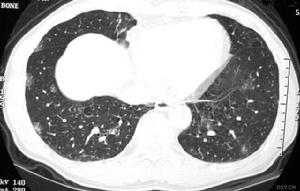

沙雷菌肺炎體徵

沙雷菌肺炎2.體徵雙肺可聞及乾濕性囉音,當肺葉或肺段出現實變時,可有相應肺段、肺葉的語顫增強,叩濁、可聞及支氣管呼吸音。危重病人可能有呼吸急促、發紺及休克等。